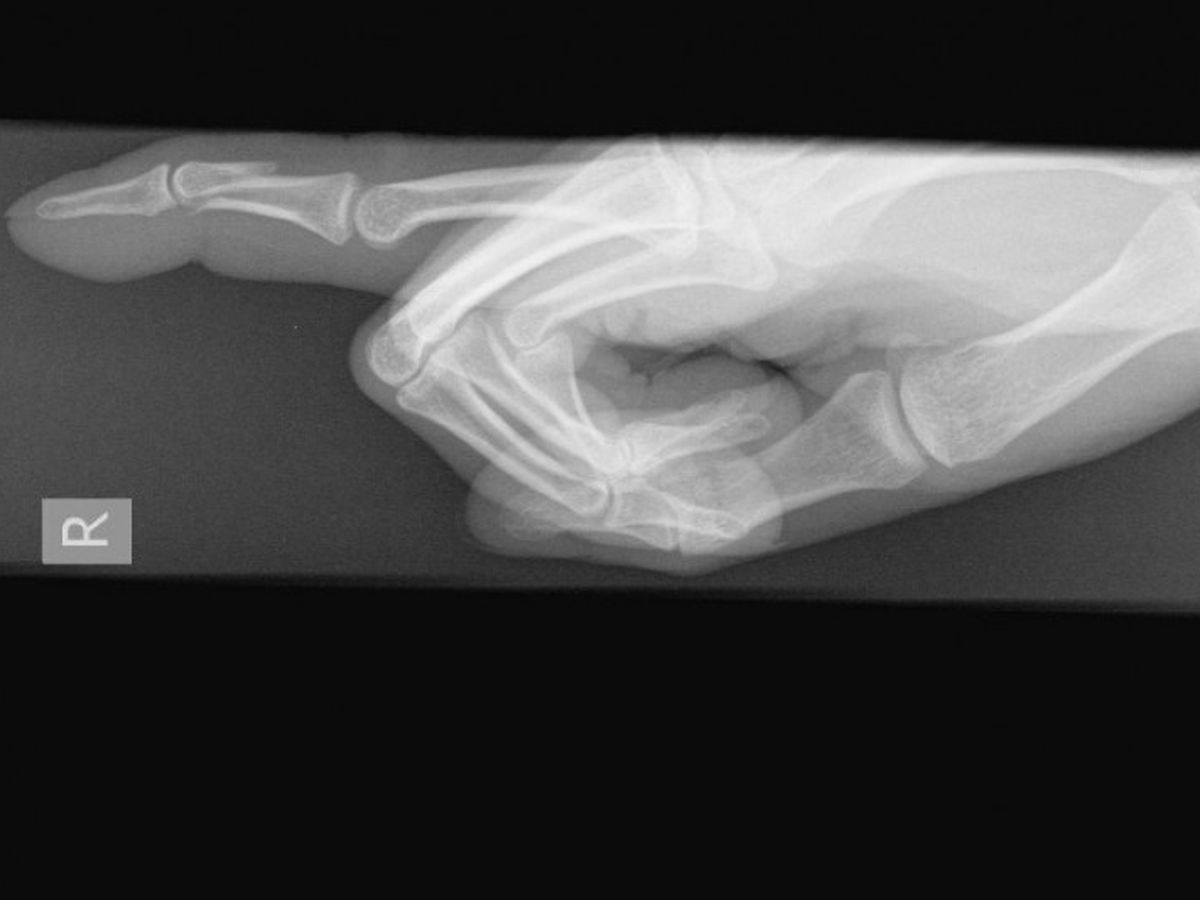

Roughly two weeks ago I smashed my finger while adventuring with friends. After 3 days of the swelling not going down  I decided to check myself into an urgent care where I was given the news that my finger was not only broken but it was broken in such a way that it required a referral to a specialist and possibly surgery.

Long story short the specialist confirmed my worst fears. I will need surgey to correct the finger and my surgery has been postponed until October 31st. For most this is a simple procedure that insurance would cover but unfortunetly through this whole ordeal I discovered my insurance policy had expired over 6 months ago. I've had to go through several different doctors as most have denied me due to being uninsured but I found a doctor who will do it for me but its going to cost $2,600 in total. I've already been paying upfront anywhere from $140-$250 for each visit I've gone to and am already more than ready to accept my fate of going into debt for the sake of getting my finger back to normal function.

With that being said I'd like to ask for help with paying for the surgery. While my injury is not life threatening it will affect the quality of my life as the finger is not only broken but slightly inverted causing very limited movement and if it heals like this my right hand would be disabled.